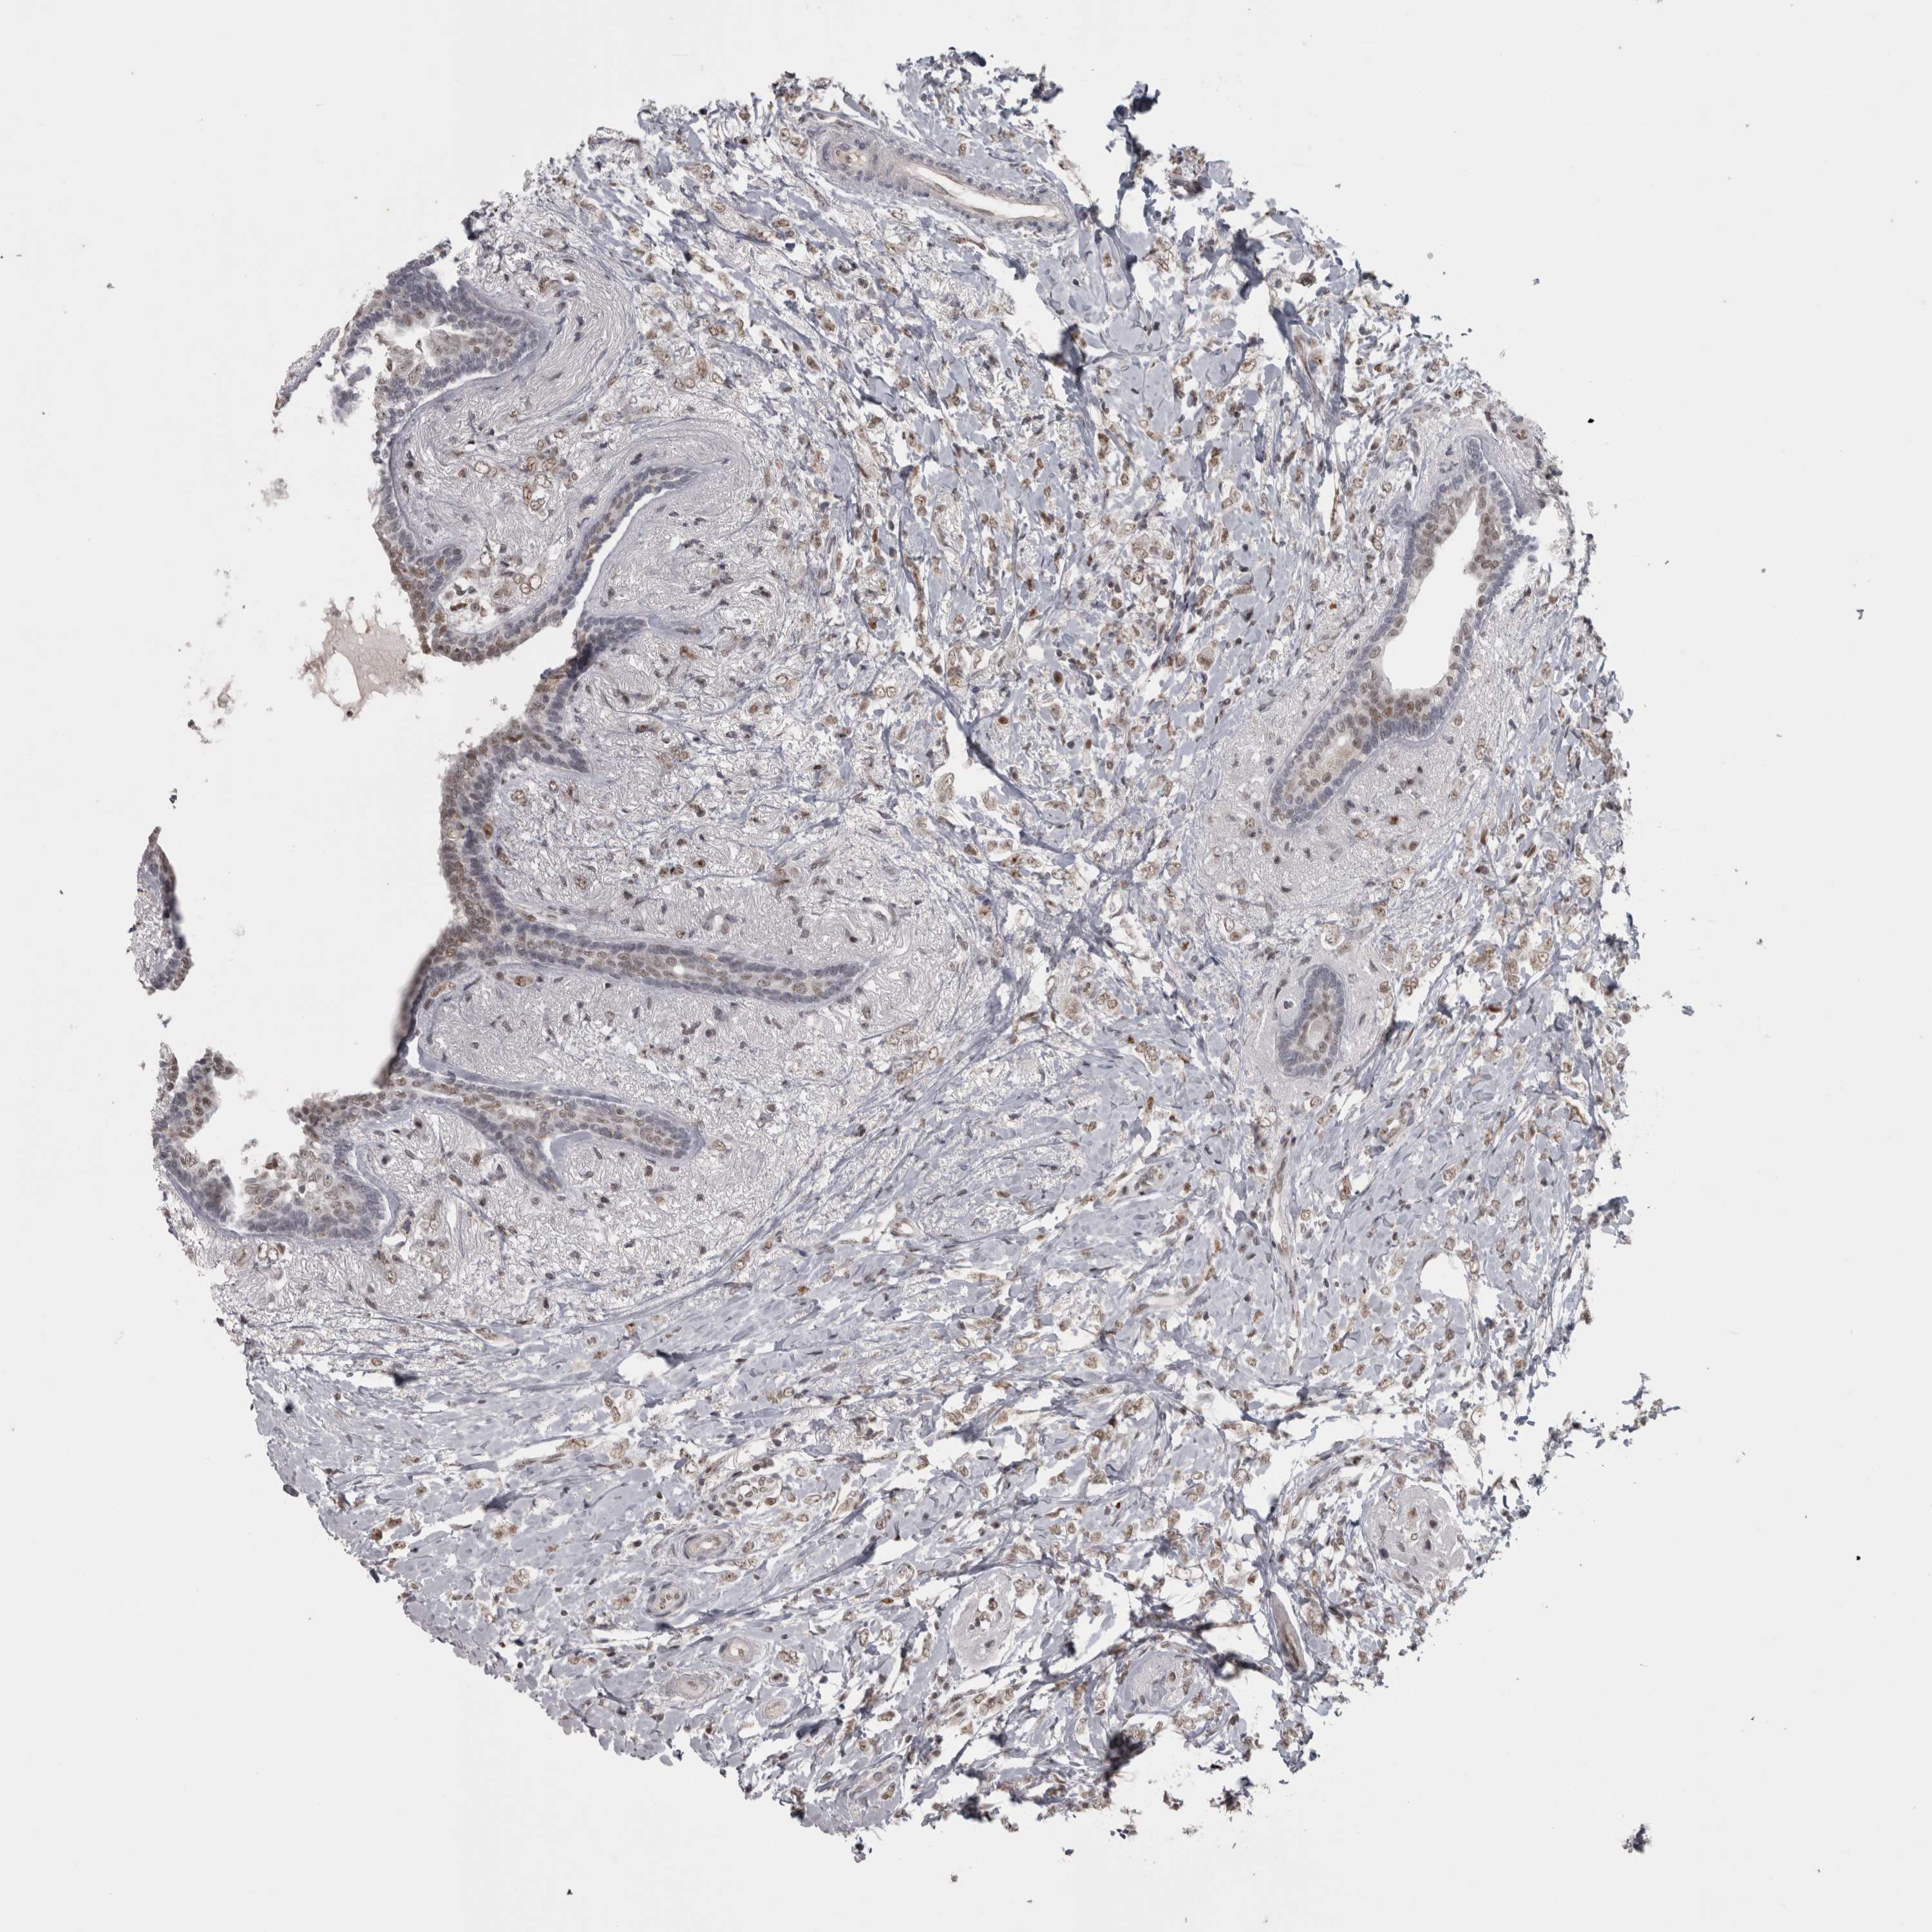

CANCER BREAST CANCER Show tissue menu

BRCA TCGA BRCA VALIDATION PROTEIN EXPRESSION

ANTIBODIES

AND

VALIDATION